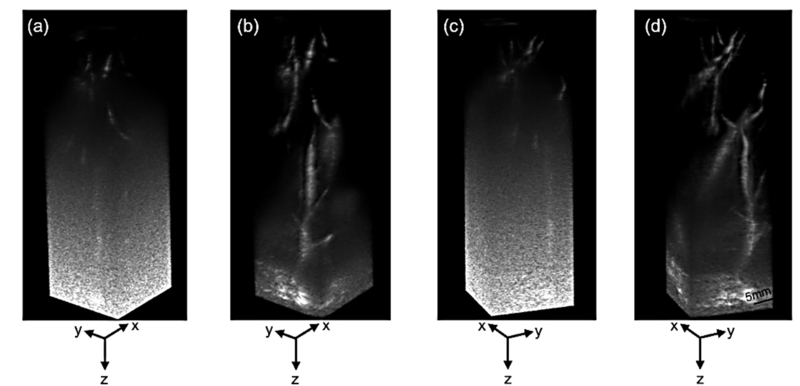

RCA 방식은 하드웨어가 단순해지는 장점이 있지만 신호 감도와 영상 품질이 떨어지는 문제도 있었다. 연구팀은 여러 각도에서 영상을 합성하는 평면파 기법을 정밀하게 최적화하고 신호 세기를 높이는 ‘코드화 여기(Coded Excitation)’ 기술을 결합해 이 한계를 극복했다. 그 결과 조영제 없이도 피부 아래 약 7cm 깊이의 혈관을 고해상도로 영상화하는 데 성공했다.

연구팀은 건강한 성인의 간과 비장을 대상으로 생체 실험을 진행해 초당 27프레임 속도로 혈류의 움직임을 실시간 포착했으며, 기존 대비 대조도-잡음비(CNR)가 약 9~10dB 향상되는 성능을 확인했다. 또한 미국 FDA 및 IEC 기준에 따른 안전성 검증에서도 장시간 촬영 시 프로브 과열 없이 안정적인 에너지 수준을 유지함을 입증했다.